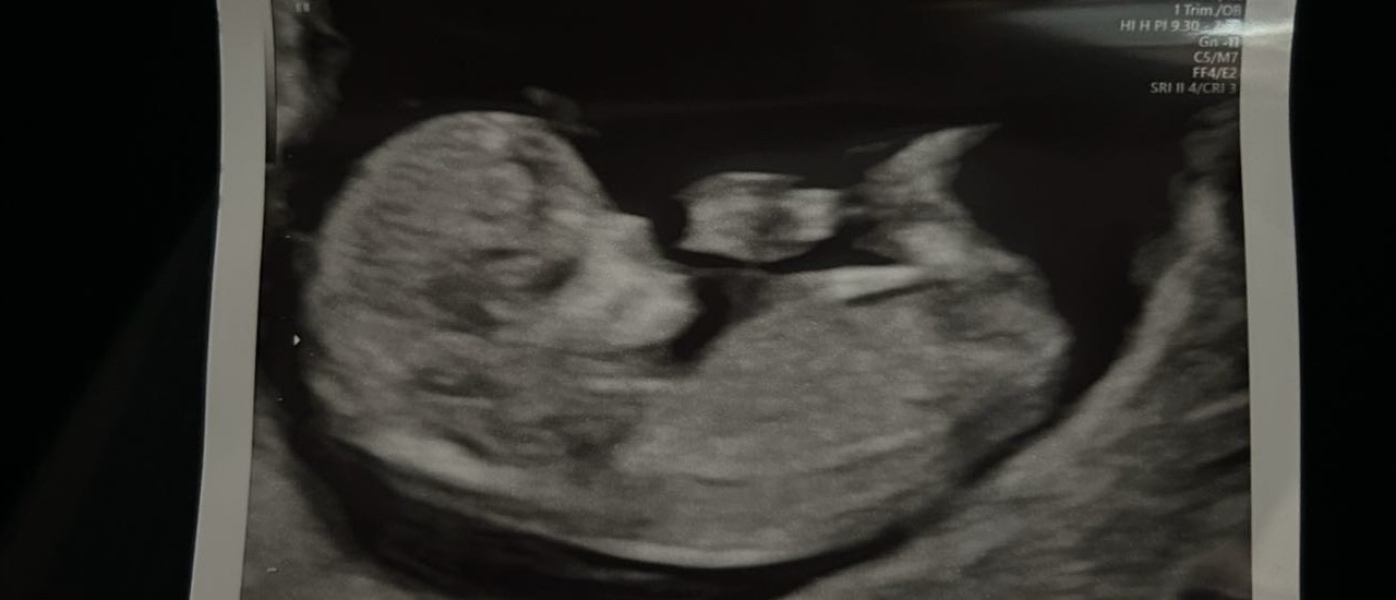

Nub theory guesses??? 11+4

Unsure if this is clear enough to tell at 11 weeks 4 days! Any guesses??

ShowmetheBotox · 26/10/2024 12:17

There is no nub on here lovely